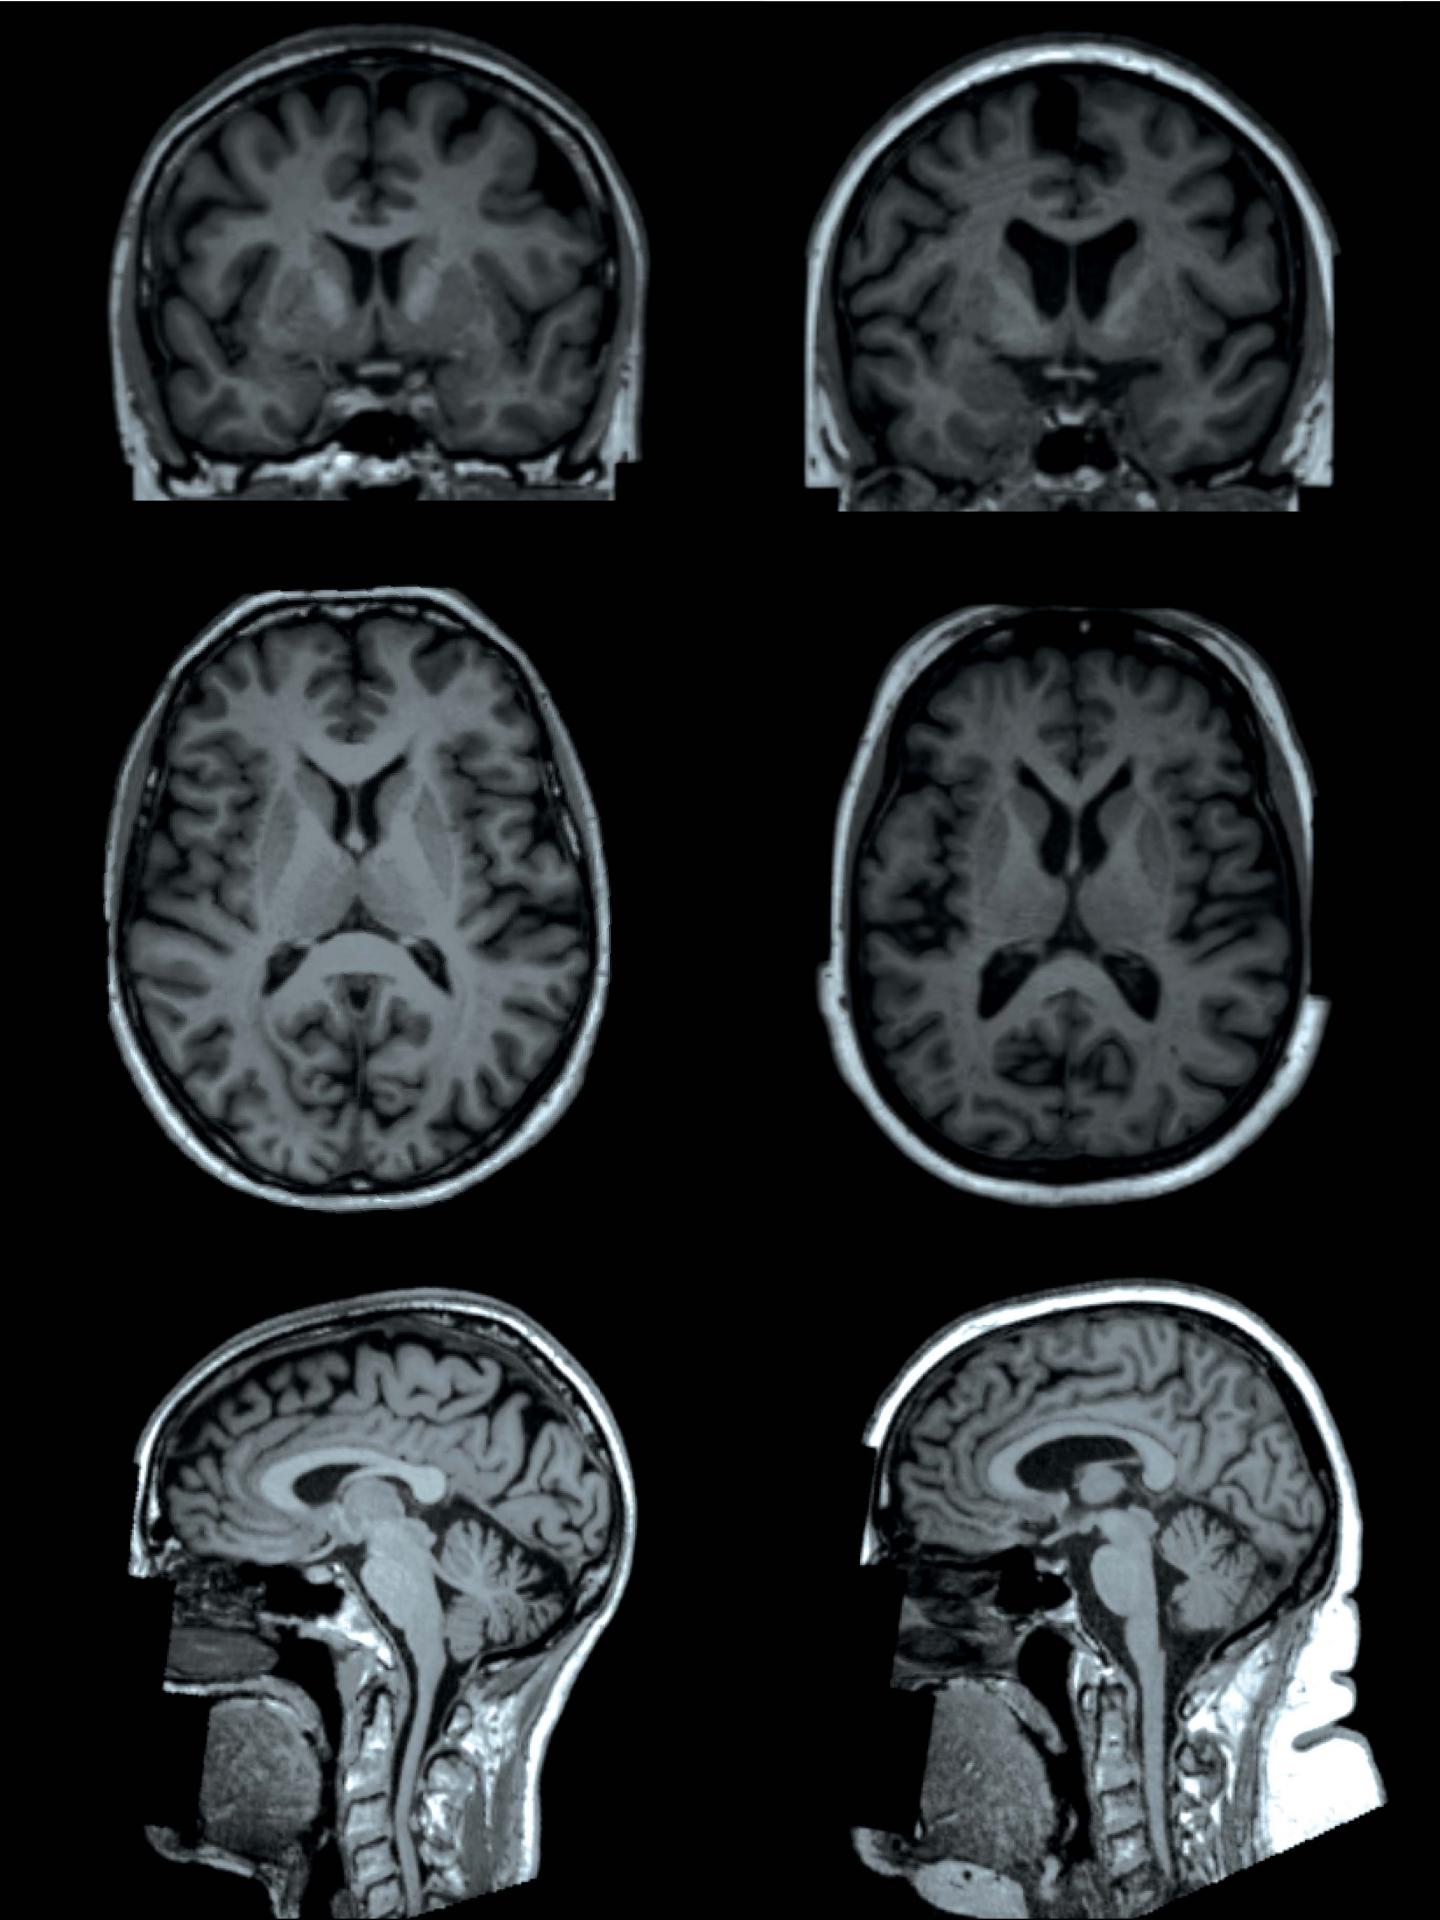

OAK BROOK, Ill. - Researchers using sophisticated MRI technology have found that higher levels of body fat are associated with differences in the brain's form and structure, including smaller volumes of gray matter, according to a study published in the journal Radiology . The findings add important information to our understanding of the connection between obesity and negative health consequences such as dementia.

"MRI has shown to be an irreplaceable tool for understanding the link between neuroanatomical differences of the brain and behavior," said study lead author Ilona A. Dekkers, M.D., from Leiden University Medical Center in Leiden, the Netherlands. "Our study shows that very large data collection of MRI data can lead to improved insight into exactly which brain structures are involved in all sorts of health outcomes, such as obesity."

To learn more about these changes, the researchers analyzed brain imaging results from more than 12,000 participants in the UK Biobank study, a major trial begun in 2006 to learn more about the genetic and environmental factors that influence disease. The brain scans used sophisticated MRI techniques that provided information on both the neuron-rich gray matter and the white matter, often referred to as the wiring of the brain.

The results show some clear associations in the patients between body fat percentage and brain form and structure, also known as its morphology.

"We found that having higher levels of fat distributed over the body is associated with smaller volumes of important structures of the brain, including gray matter structures that are located in the center of the brain," Dr. Dekkers said. "Interestingly, we observed that these associations are different for men and women, suggesting that gender is an important modifier of the link between fat percentage and the size of specific brain structures."

Analysis showed that, in men, higher total body fat percentage correlated with lower gray matter volume overall and in specific structures involved in the reward circuitry and the movement system. In women, total body fat only showed a significant negative association with the globus pallidus, a structure involved in voluntary movement. For both men and women, higher total body fat percentage increased the likelihood of microscopic changes to the brain's white matter.

The ramifications of these findings, not yet fully clear, could be of significant importance. Smaller gray matter volume suggests loss of neurons, and changes to the white matter could adversely affect the transmission of signals within brain networks. Since the smaller subcortical grey matter volumes are also known to play a role in the food-reward circuitry, these changes may also make it more difficult for obese people to control their weight, Dr. Dekkers said, although more research will be needed to support that connection.